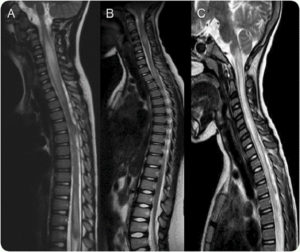

روش های تشخیصی

- MRI